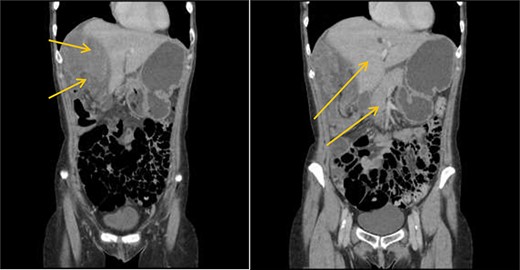

Patient initially diagnosed as biliary colic and surgical team had been contacted. Plain Abdominal radiograph showed dilated small bowels loops (Fig. 1). Chest radiograph revealed air under right hemi-diaphragm (Fig. 2). CT scan was done in emergency department and confirmed interposition of bowel between the diaphragm and the liver with a vascular/mesenteric pedicle swirl suggestive of malrotation or volvulus of the right colon. There was marked mural thickening and bold dilatation with high attenuation mucosa in keeping with closed loop obstruction and possible necrosis (Figs 3 and 4).

CT scan shows interposition of ileum, cecum and ascending colon between liver and diaphragm pushing right loop of the liver and gallbladder medially.

CT scan shows a vascular/mesenteric pedicle swirl suggestive of malrotation or volvulus with evidence of dilated closed loop obstruction.